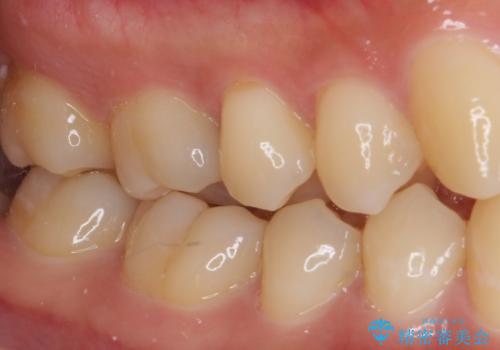

フロスが引っかかる セラミックインレーによるむし歯治療

- ウェブサイトの症例(https://seimitsushinbi.jp/case/9473/)を見て、同じようにフロスが引っかかるとのことで来院された患者様です。

虫歯を除去した後、セラミックインレーにて修復治療を行うこととしました。

セラミックインレー装着後はフロスの引っかかるストレスから解放され、患者様には大変満足していただきました。